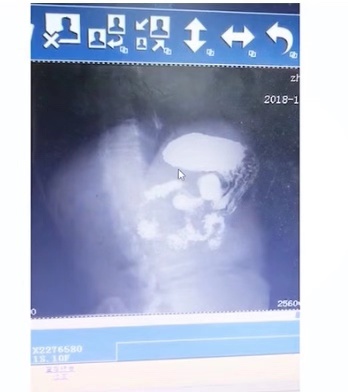

患者也曾去耳鼻喉就诊,用了很多治嗓子的药也没有效果。后来来我们胃食管反流病诊疗中心做钡餐就报了一个稀释,也没有发现反流。但患者所表述的一系列症状都是与胃食管反流对应的,我们认真评估了患者的钡餐,认为是有食管裂孔疝的,但需要通过测压测酸来证实。

(钡餐报告)